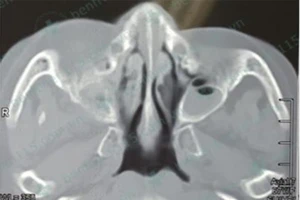

Nguy cơ tử vong vì viêm xoang trên bệnh nhân tiểu đường